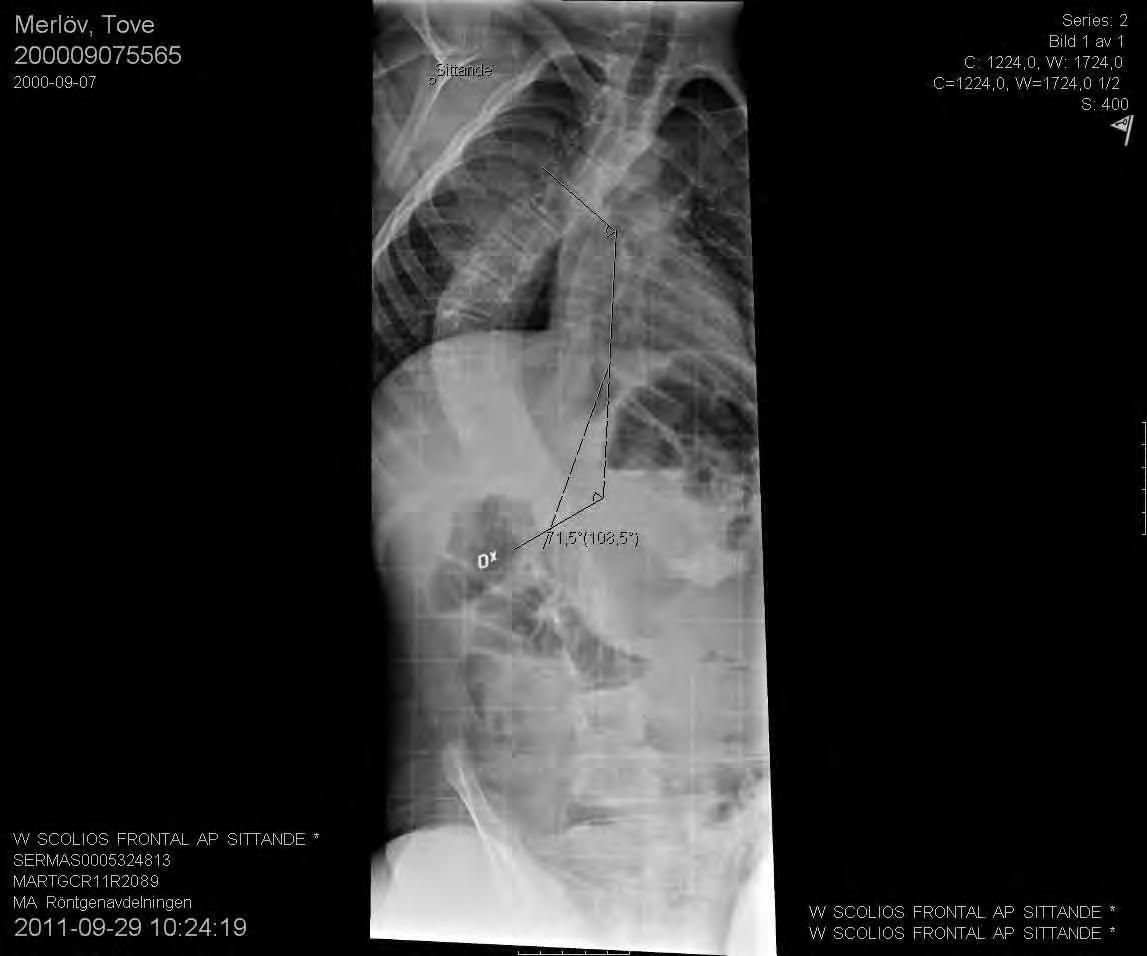

Neuromuskulära skolioser är ofta komplicerade och svåra att behandla. I allmänhet uppträder dessa ryggradsdeformiteter ganska tidigt, de blir snabbt stela och är progressiva. Ofta resulterar de i ett snedställt bäcken och kan också innefatta en svår sagittal inbalans som gör att de utgör ett stort hinder för normal funktion.

Av Acke Ohlin

Den kirurgiska behandlingen vid neuromuskulär skolios är den hittills enda kända metoden för att stoppa progress.

Skolios uppträder i ungefär hos var fjärde patient med CP. Ju mer spastisk patienten är, desto större är risken för svår deformitetsutveckling. Hos patienter med kvarstående gångfunktion är behandlingen ofta helt likartad den vid idiopatisk skolios. Patienter med CP har ofta längre tid för skoliosutveckling då deras skelettala mognad äger rum något senare än normalt. Vid skelettal mognad är risken för fortsatt progress 0,8 grader per år vid krökar som är mindre än 50 grader enligt Cobb och 1,4 grader när kröken överstiger 50 grader. Den goda effekten av Baklofen är observerad framför allt vid spasticitet i extremiteterna men det finns inte något säkert vetenskapligt stöd för dess effekt på utvecklingen av ryggradsdeformiteten även om det allmänna välbefinnandet blir bättre.

11-årig flicka med CP och spastisk tetrapares. Hon hade en extremt snabb skoliosutveckling från Cobb 45 grader till drygt 70 grader på tre månader. detta föranledde en snar op från Th2 till L5 med transpedikulära skruvar enl. Suk. Blödningen uppgick till 1500 ml. Postoperativt har vi inga restriktioner avseende mobiliseringen då så många fixationspunkter användes. Patienten hade postoperativt lunginflammation som dock snabbt svarade på antibiotikabehandling.

Preop PA sittande visar en 65-gradig skolios enligt Cobb.